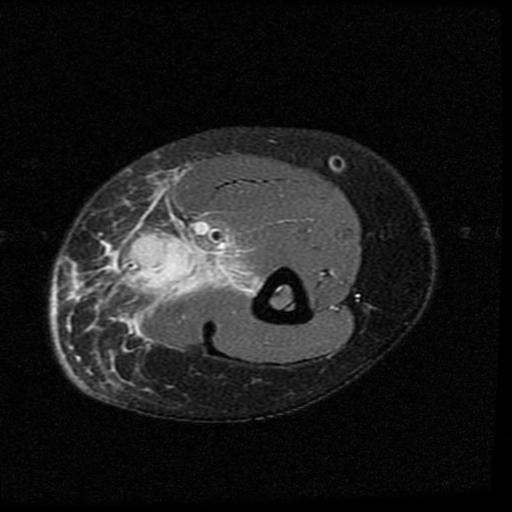

Figure 1 for case cat scratch disease

Figure 1